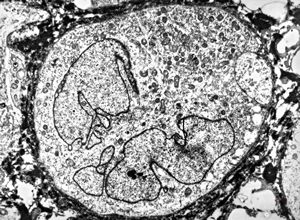

normal seromucinous salivary gland